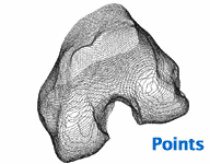

The process for studying natural knees is more difficult since CAD models of the bones are not readily available. To create models of natural knees, Fregly’s team uses CT scans, which produce static 2D image slices from the top to the bottom of a patient’s leg. The CT data are then imported into sliceOmatic image-processing software from TomoVision, where a 3D point cloud model is created by stacking the 2D axial images of patients’ legs.

Beyond Point Cloud Data

When studying natural knees with fluoroscopy, the problem becomes how to turn the point cloud data obtained from sliceOmatic into accurate 3D models of the bone surfaces. Banks requires highly detailed surface models - the more precise the surface representation, the better the fluoroscopic image-matching results.

“We need to go beyond point cloud data and develop accurate representations of the curves and contours inherent in an organic, biological surface,” says Fregly. “Most off-the-shelf engineering tools are not adequate for this purpose.”

Segmented CT scan slices are stacked to form a point cloud model of the femur